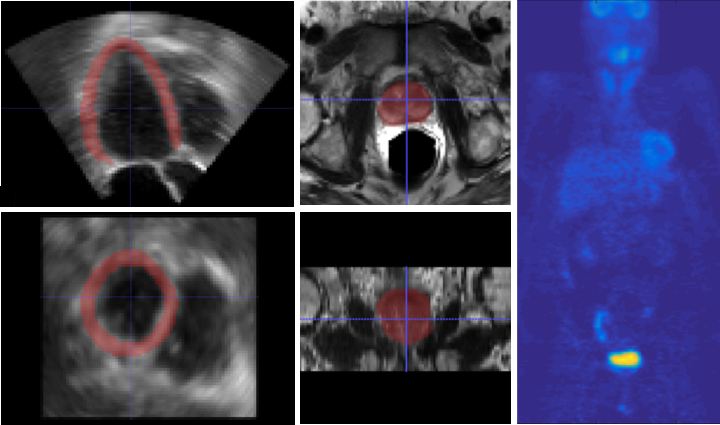

For evaluation, we use three different datasets: a) 58 whole body PET scans of resolution . We randomly pick 10 whole body volumes for testing and train with the 48 remaining volumes. We normalize the intensity range of our training and testing volumes using the min-max method based on min and max intensity values of the whole training set. Next, in both training and testing, each single sub-volume is also normalized to using its min and max before feeding it into network. b) 958 MRI prostate scans of different resolution which were resampled to voxel size of . We randomly picked 258 volumes for testing, and train with remaining 700 volumes. c) hlUltrasound echocardiography images of resolution , used for left ventricular myocardial segmentation, were split into 430 train and 20 test. The datasets were collected internally and from The Cancer Imaging Archive (TCIA) QIN-HEADNECK and ProstateX datasets [26, 27, 28, 29, 30]. Samples of the three datasets are shown in Fig. 2.

V-B Performance of the proposed vs. competing methods on single organ segmentation from MRI and ultrasound

For MRI and ultrasound datasets, we observed that all the methods are more prone to false negatives than false positives, so we weigh more the false negative term of the proposed loss (i.e., increase to 0.9). As reported in Table V, similar to results in Section V-A, the Combo loss function improved 3D U-Net and 3D V-Net by 4.6% and 1.13% in Dice and 43.8% and 16.7%in FNR, respectively, for MRI prostate segmentation. Similarly, 3D U-Net and 3D V-Net results were improved by 8.23% and 3.4% in Dice and 33.3% and 16.7%in FNR, respectively, for ultrasound left ventricular myocardial segmentation.

Among the competing methods, U-Net applies cross entropy loss while V-Net leverages Dice loss. To show the direct contribution of the Combo loss, we replace the original loss functions in U-Net and V-Net with Combo (Table V). As reported in Table V, after replacing cross entropy loss of U-Net with Combo loss, the Dice scores improve from 0.87 to 0.91 and 0.85 to 0.92 for MRI and ultrasound datasets, respectively. Similarly, when replacing the Dice loss function of V-Net with the proposed Combo loss, the segmentation results improve from 0.88 to 0.89 and 0.84 to 0.87 for MRI and ultrasound datasets, respectively.